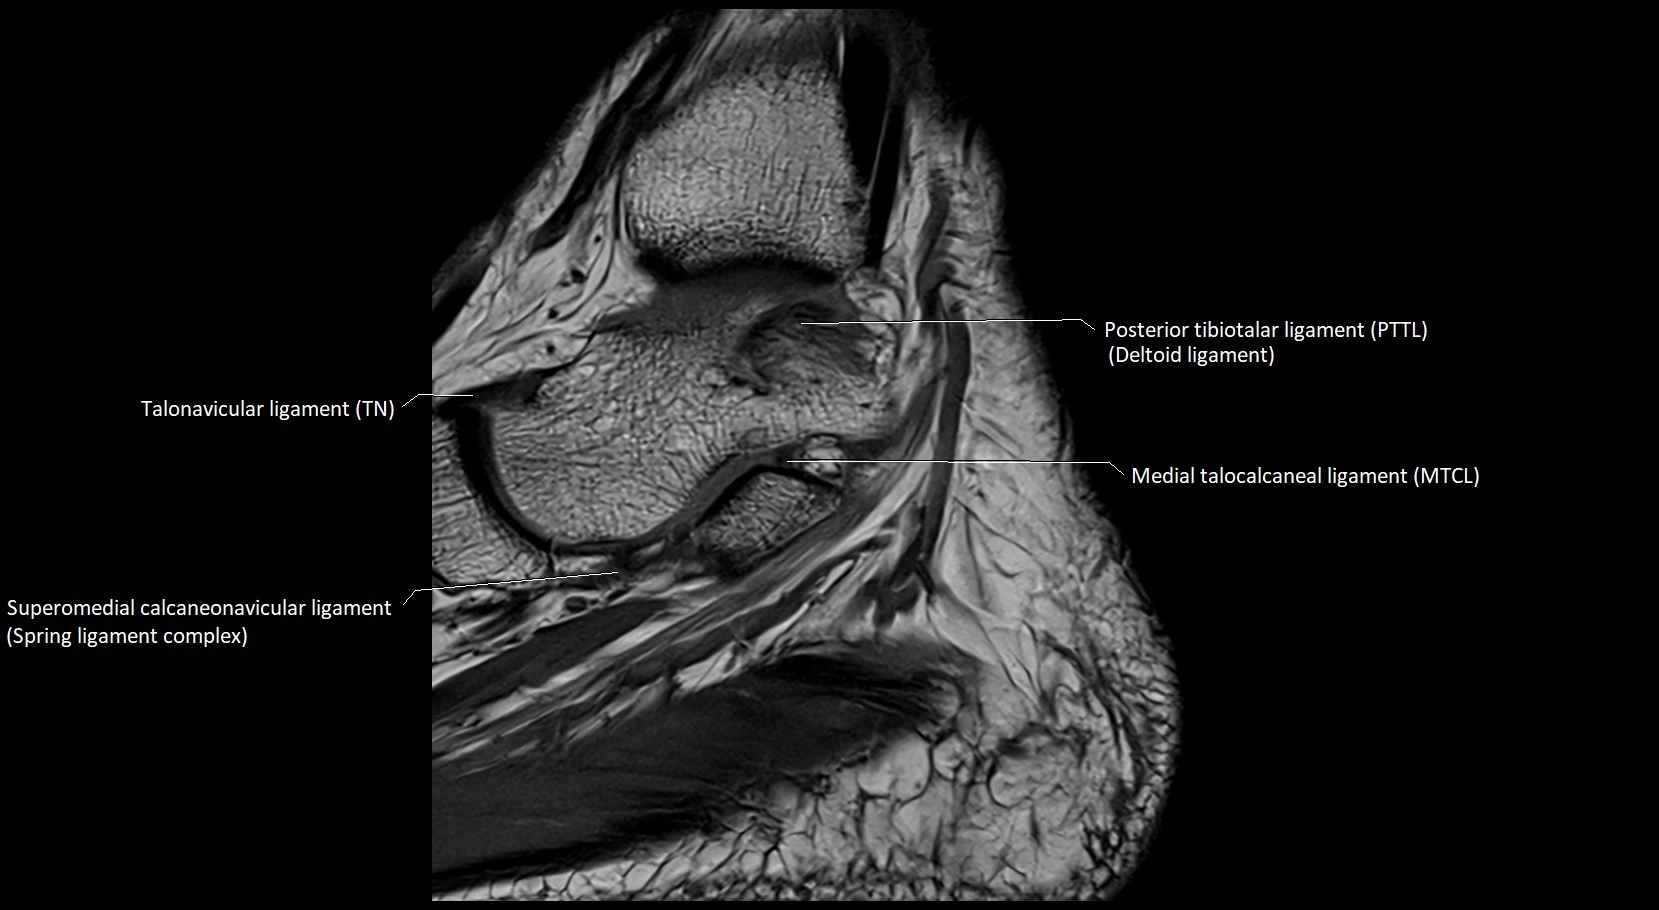

MRI image

image